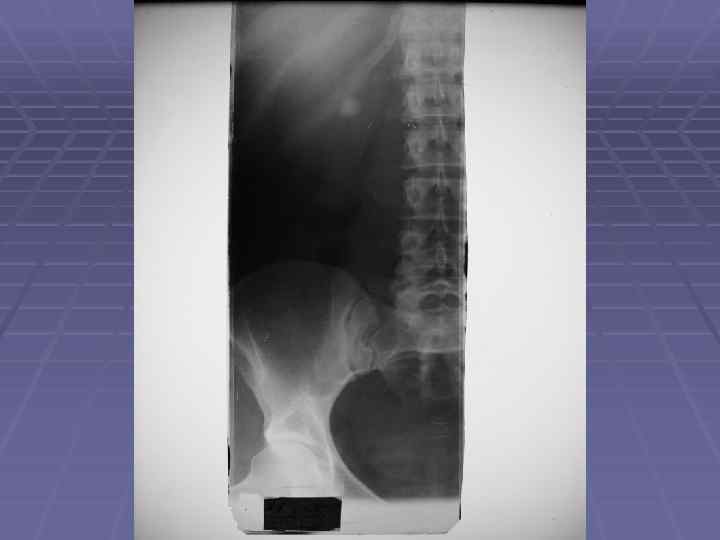

На рентгенограмме верхняя граница почки обычно располагается на уровне XI грудного позвонка, нижняя — на уровне III поясничного позвонка. Верхний полюс почки достигает XI ребра, а нижний расположена на 3— 5 см выше гребешка подвздошной кости. Тень левой почки обычно расположена выше правой на 1 -2 см и делится XII ребром пополам, в то время как тень правой пересекается XII ребром на границе верхней и средней третей.

У детей почки относительно велики, тогда как поясничная часть позвоночника сравнительно коротка. В силу этого у детей на рентгенограммах тень нижнего полюса почек расположена весьма близко к гребешку подвздошной кости, а иногда находится на уровне его. Такое низкое расположение у детей почек связано и с тем, что правая почка занимает свое окончательное положение в поясничной области в возрасте 5 -7 лет, а левая 8 -10 лет.